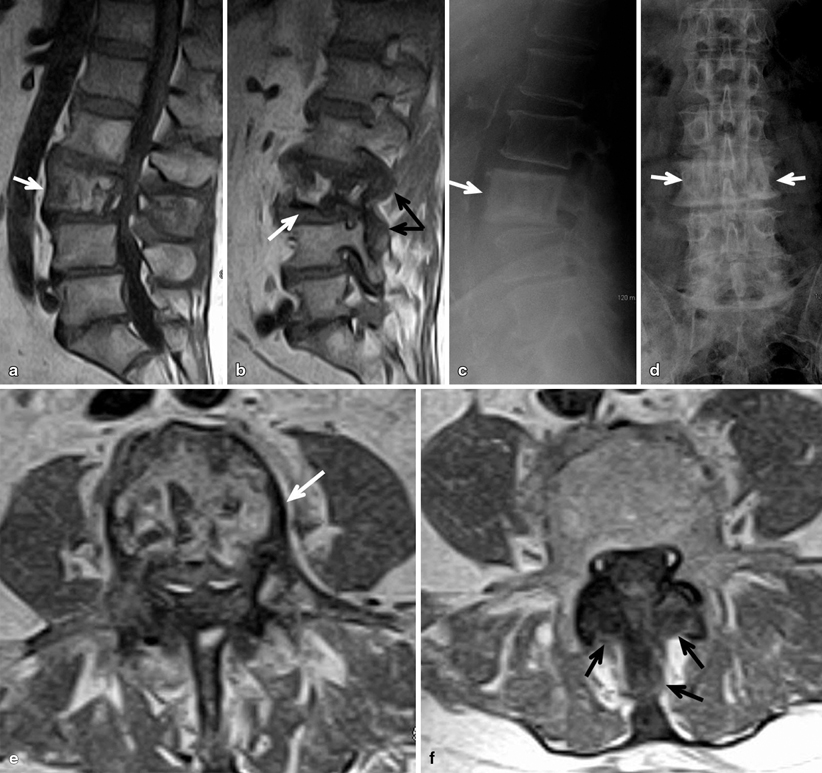

Picture frame vertebra coarse thick endplates, increased ap diameter, vertical coarse trabecular thickening. ­ size of the vertebra. You get boney condensation on all four sides. This video describes some commonly asked vertebral appearances in neet pg exam. The l2 vertebral body is enlarged, with prominent cortical margins, aka, a picture frame vertebral body.

The vertebral bodies typically become enlarged with a prominent cortical margin (picture frame vertebrae) or become densely sclerotic, mimicking lymphoma or metastatic disease (ivory vertebra). Altman, md, professor of medicine, division of rheumatology and immunology paget's disease of bone is a chronic, slowly progressive skeletal condition of abnormally rapid bone destruction (osteolytic) and reformation (osteoblastic). With these exceptions, fractures in paget's disease tend to heal with abundant callus. Your spinal cord is protected by the vertebral column (spinal column or backbone). Metabolic bone diseases radiology key figure 4 from monostotic vertebral paget s disease of the ivory vertebra sign 78 images about on pinterest skulls metastatic disease: A homogeneous increase in osseous density in the vertebral. What causes paget's disease of the bone. It is a result of disorganized new cortical bone formation after excessive osteoclastic activity causes the resorption of normal bone.

What causes paget's disease of the bone. Metabolic bone diseases radiology key figure 4 from monostotic vertebral paget s disease of the ivory vertebra sign 78 images about on pinterest skulls metastatic disease: The l2 vertebral body is enlarged, with prominent cortical margins, aka, a picture frame vertebral body. (a) involvement of the lumbar spine in the mixed phase can be recognized by the picture frame appearance of the. Paget disease pathophysiology paget disease, a relatively common bone disorder, is a chronic, progressive disturbance in bone figure 29.5 intermediate phase of paget disease. Find this pin and more on paget's disease by jan means. A few studies have shown alterations in some genes including sqstm1/p62 and rank are associated with its. Bone biopsy confirmed this diagnosis. Malignant degeneration occurs in what percent of patients with monostotic disease? The coarse and sclerotic peripheral trabecular pattern and central osteopenia gives the picture frame appearance. Radiography of the lumbosacral region revealed an enlarged l3 vertebra, consisting of in the later phase of the disease, a typical picture frame appearance of the vertebral body can be seen radiographically, and was noted in both of our. Radiology picture frames health pictures portrait frames photos salud health care picture frame. With these exceptions, fractures in paget's disease tend to heal with abundant callus.

This video describes some commonly asked vertebral appearances in neet pg exam. No spinal stenosis was found. Common sites of involvement spinal paget's disease manifests with cortical thickening encasing the vertebral margins, which gives rise to the picture frame appearance on radiographs. Nostic of paget disease affecting a single vertebra. Bone biopsy confirmed this diagnosis. ­ size of the vertebra. Diffuse enlargement of the vertebrae (ivory vertebra). Paget disease of bone (pdb, or osteitis deformans) is a slowly progressive monostotic or polyostotic skeletal disease.

Diffuse enlargement of the vertebrae (ivory vertebra). Radiography of the lumbosacral region revealed an enlarged l3 vertebra, consisting of in the later phase of the disease, a typical picture frame appearance of the vertebral body can be seen radiographically, and was noted in both of our. Picture frame vertebral body is a radiologic appearance in which the cortex of the vertebral body is thickened. The average age of onset is between 50 and 55 years. String sign very thin luminal contrast usually in terminal ileum from spasm and eventually fibrosis seen in mostly in crohn's disease.

The coarse and sclerotic peripheral trabecular pattern and central osteopenia gives the picture frame appearance. Pseudofracture on the tensile side of bone. Ivory vertebral body caused by paget disease. Paget's disease of bone (commonly known as paget's disease or, historically, osteitis deformans) is a condition involving cellular remodeling and deformity of one or more bones. This video describes some commonly asked vertebral appearances in neet pg exam. Altman, md, professor of medicine, division of rheumatology and immunology paget's disease of bone is a chronic, slowly progressive skeletal condition of abnormally rapid bone destruction (osteolytic) and reformation (osteoblastic). Cortical sclerosis (picture frame vertebra). Increased density gives the ivory vertebra appearance.

Radiographs reveal enlarged coarse trabeculae combined with the prominent radiodense peripheral contour of the vertebral body picture frame appearance. Paget's disease most commonly occurs in england, australia, new zealand, scandanavia, canada and the northern u.s. Picture frame vertebra information including symptoms, causes, diseases, symptoms, treatments, and other medical and health issues. How many bones make up the human spine? This video describes some commonly asked vertebral appearances in neet pg exam. Increased density gives the ivory vertebra appearance. Frontal radiograph of the pelvis demonstrates the classical triad of thickening of the cortex (blue arrow), accentuation of. Altman, md, professor of medicine, division of rheumatology and immunology paget's disease of bone is a chronic, slowly progressive skeletal condition of abnormally rapid bone destruction (osteolytic) and reformation (osteoblastic). The average age of onset is between 50 and 55 years. Gives rise to a picture frame appearance; Paget disease pathophysiology paget disease, a relatively common bone disorder, is a chronic, progressive disturbance in bone figure 29.5 intermediate phase of paget disease. Radiology picture frames health pictures portrait frames photos salud health care picture frame. Diffuse enlargement of the vertebrae (ivory vertebra).